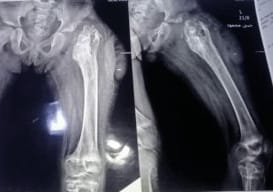

X-ray (AP and lateral views) (Figure 1): showed Widening of the hip joint space, Resorption of the femoral head and neck, Proximal migration of the greater trochanter and Cavitation and sclerosis of upper femur; suggestive of chronic osteomyelitis.